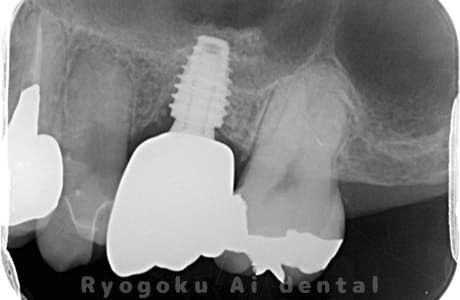

Case07

- 原因

- 右下6番歯根破折

-

- 治療内容

- インプラント治療

- 治療費用

- 約600,000円

右下の腫れが治らないとの事でご来院された患者様です。歯が割れていたため、抜歯を行い、骨に代わるお薬を入れ、インプラントを埋入致しました。経過良好で大変満足していただけました。

<リスク・副作用>

治療後、痛みや違和感、出血、腫れなどが出る事があります。喫煙者、糖尿病などの方の場合、歯が生着しない場合があります。